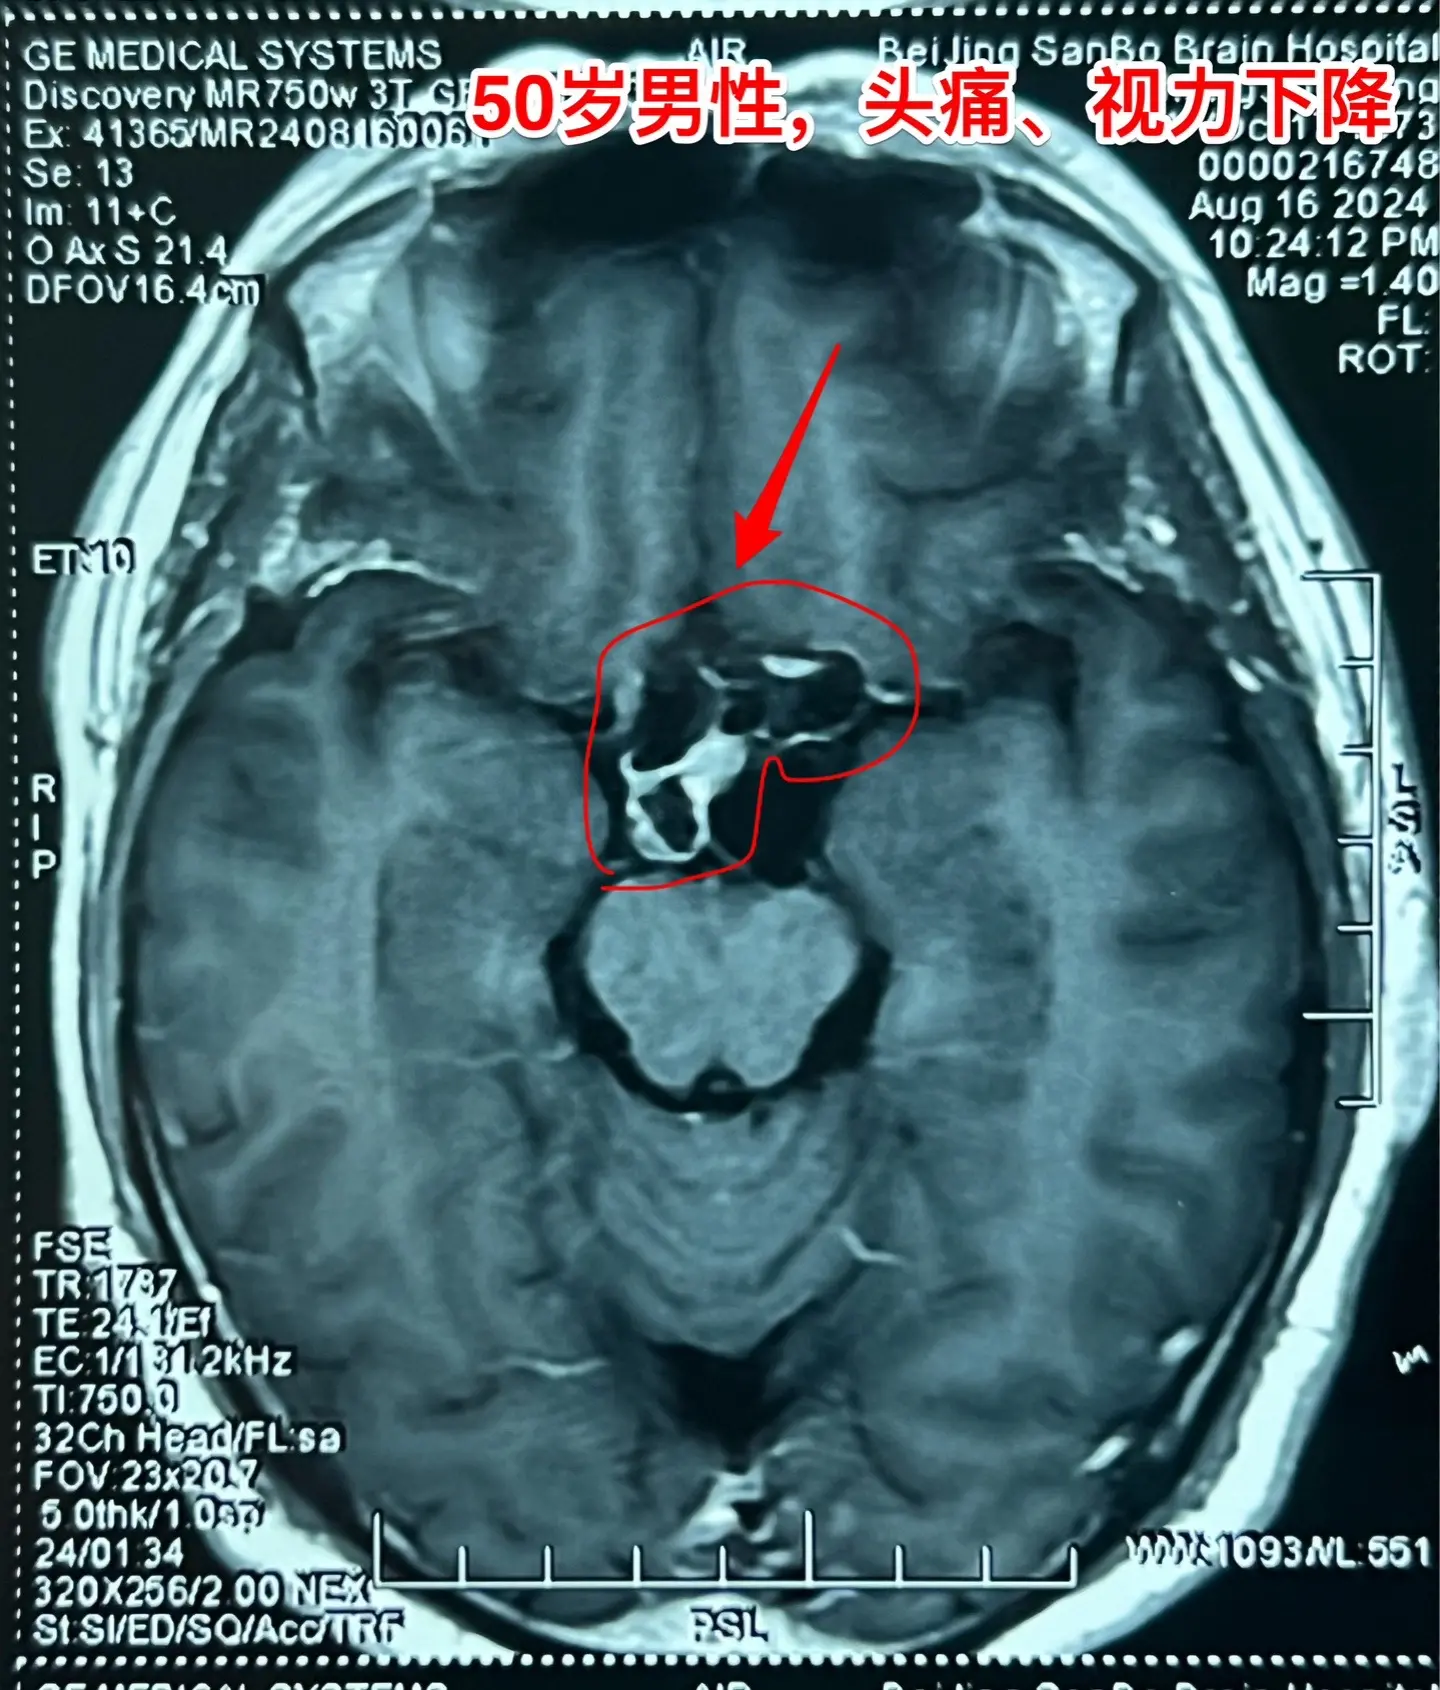

颅咽管瘤手术,出院3天就开车,合适吗?50岁的山东临沂男性,因头痛一年,左眼视力下降三个月于2024.8.16在我科住院。左眼视力0.1,右眼视力1.0。8月22日行开颅手术切除颅咽管瘤,手术后视力改善,身体恢复顺利,9月2日出院了,出院前测左眼视力0.5,右眼1.0。出院时精神好,体力好。 9月8日患者女儿和我联系,说患者出院三天就开车了。我告诉她,需要复查视力和视野,如果视野有缺损,开车是有风险的,不适合开车。